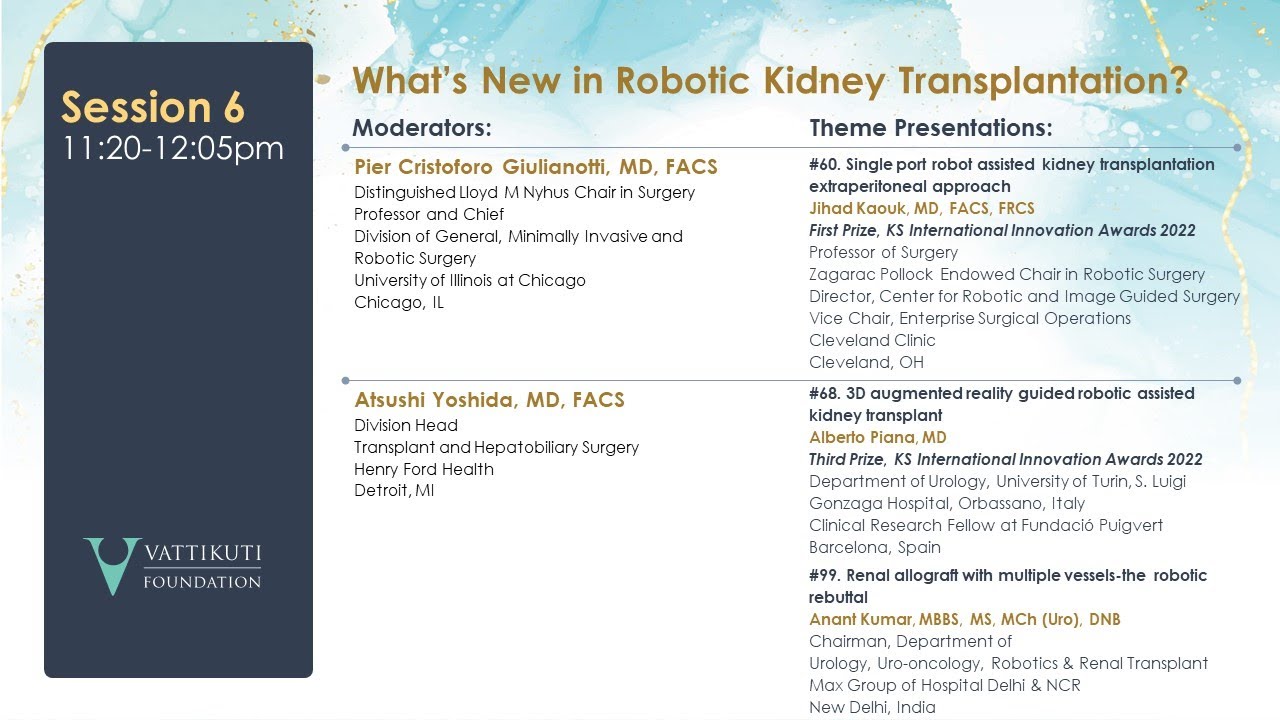

Single Port Robot-Assisted Kidney Transplantation: Extraperitoneal Approach

3D Augmented Reality Guided Robotic-Assisted Kidney Transplantation

RENAL ALLOGRAFT WITH MULTIPLE VESSELS – THE ROBOTIC REBUTTAL